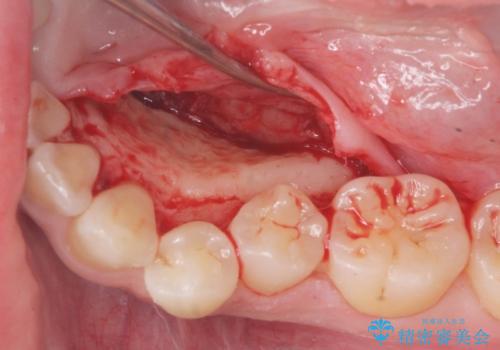

上下の歯のがたつきを改善するマウスピース矯正治療と、下顎に見られる大きな骨隆起を外科的に除去する治療計画を進めていきます。

骨隆起の除去は、静脈内鎮静法を用いてほとんど記憶のないうちに行うことができます。

- 外科手術のため、術後に出血、痛みや腫れ、違和感を伴います